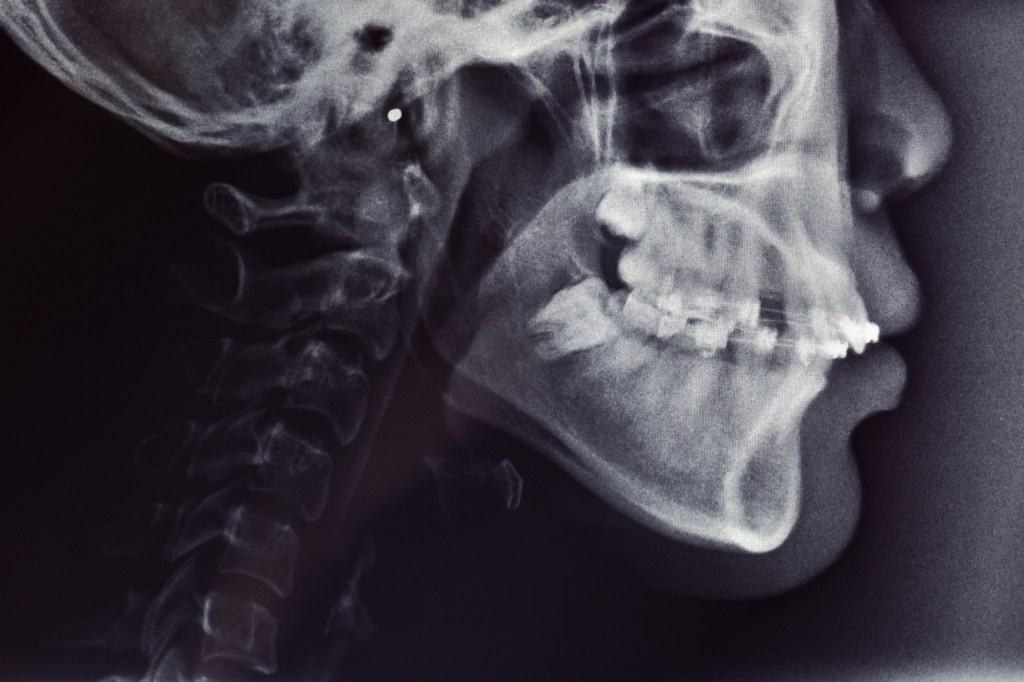

Os distúrbios temporomandibulares (DTMs) afetam a articulação que conecta a mandíbula ao crânio e são responsáveis por movimentos como abrir e fechar a boca. Os principais sintomas incluem dor na mandíbula, estalos ao abrir a boca, dificuldades para movimentar a mandíbula, dores de cabeça, dor no pescoço e ombros, e até zumbido nos ouvidos.

As causas mais comuns destes distúrbios incluem bruxismo (ranger ou apertar os dentes), lesões na mandíbula, desalinhamento dentário, hábitos parafuncionais (como por ex: roer unhas) stress que provoca tensão muscular, e condições inflamatórias como a artrite. Esses fatores podem levar a um desgaste da articulação ou ao mau funcionamento dos músculos e ligamentos da região.

O tratamento varia conforme a gravidade do caso, e pode incluir o uso de placas orais interpostas entre a maxila e a mandíbula, para reduzir os efeitos do bruxismo permitindo- se o relaxamento da musculatura, fisioterapia para melhorar a mobilidade e aliviar a dor, e medicações como analgésicos ou anti-inflamatórios e relaxantes musculares. Mudanças no estilo de vida, como técnicas de relaxamento para reduzir o stress, também podem ser recomendadas. Em casos mais graves, quando os tratamentos conservadores não são eficazes, pode ser necessário realizar cirurgia, embora isso seja raro.